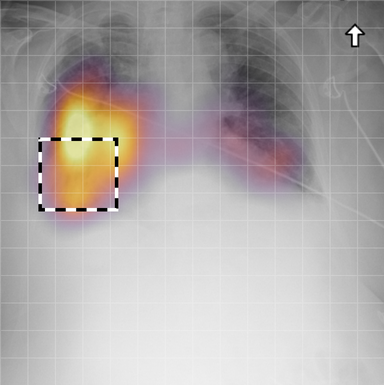

for , where denotes 2D sinusoidal positional encodings [12] and is its temporal counterpart, which is learnt (Fig. 2) [4]. The layer-normalised () [6] output of the final transformer encoder block is an ‘aggregated’ representation of patch-level progression information anchored on the current image. Figure 3 shows attention roll-out [1] applied to after pre-training, showing how the prior image contributes to the fused representation. Figure A.5 further highlights the robustness to variations in pose underlining that registration is not necessary for this encoder.

In Figure A.3, we show examples of self-attention rollout [1] maps for pleural effusion and consolidation, including radiologist-annotated bounding boxes surrounding the corresponding pathology in each prior and current image.

To model the attention flow through the transformer encoder block, we first average each attention weight matrix across all heads, subsequently we multiply the matrices between every two layers. For every block we add the identity matrix in order to model the residual connections. Last, we only keep the top 10 of attention weights per block to reduce noise in the final rollout map. In contrast to [21], we do not visualize the rollout map with respect to a [CLS] token. Instead, we choose a reference image patch from the center of the radiologist-annotated bounding boxes, marked with in Figure A.3.

We find that the rollout maps in Figure A.3 are in good agreement with radiologist-annotated bounding boxes, i.e., the reference patch attends to other patches within the bounding boxes in the prior and current image. In addition, we find that BioViL-T is robust to pose variations, e.g., in Figure A.3 (a) we show that despite the vertical shift between prior and current image, the reference patch attends to the correct image patches in the prior image.

To further assess the robustness of BioViL-T against pose variations between prior and current images, we performed multiple rotations to the prior image within a pair and computed rollout maps from the same reference patch in the current image. Figure A.5 shows that BioViL-T consistently attends to the corresponding anatomical region independently of the spatial transformation applied, demonstrating that registration is not needed.